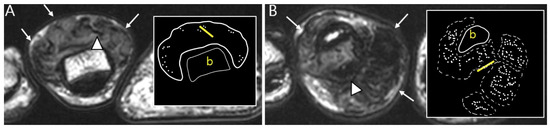

2.3. Morphological Findings for D-TSGCT

2.4. Relationship to Adjacent Structures of D-TSGCT